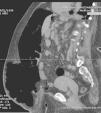

The technique involved the initial placement of a catheter within the abdominal cavity. This procedure was performed in the operating room under local anesthesia and sedation, with the initial creation of a small pneumoperitoneum with a Veress needle to insert the intraperitoneal catheter (Fig. 3) guided by either ultrasound or CT. All patients were previously admitted to the hospital and signed an informed consent form authorizing the pneumoperitoneum procedure and intervention. Immediately after the initial insertion of the catheter, the first dose of room air was injected through a device with a bacterial filter that was used daily for insufflation (double-lumen catheter similar to the one used in central lines).